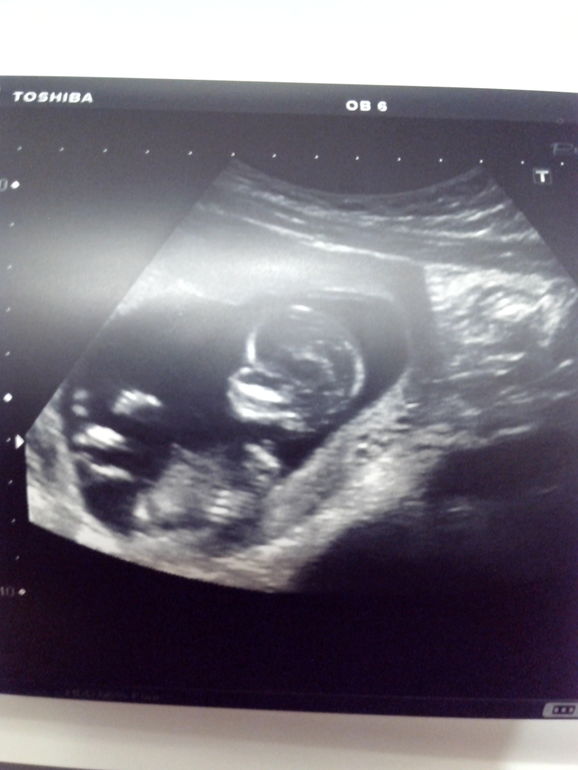

Наши будни, наши неделькиУра, время летит, малыш растет и развивается. Анализы все в норме и мой организм начитает жить в гармонии со мной и малышом, пропала тошнота и боль в груди. Но в весе я теряю. В субботу с мужем ходили на узи и смотрели нашу кроху, целая фотосессия- 5 фотографий дали. Стесняшка наш в конце упорно отворачивался и только плечи видели.

у меня 13 недель и животик я тоже не замечаю, немного появилось выпячивание в области лобка, малыш же еще крошечный. И это наш первый скрининг, делала на сроке 12,5 нед.

Удивительно, врач говорила что голова сейчас по срокам у малыша большая и т.д.По-моему нормальный человечек с небольшой головой. Главное чтобы развивался:)))